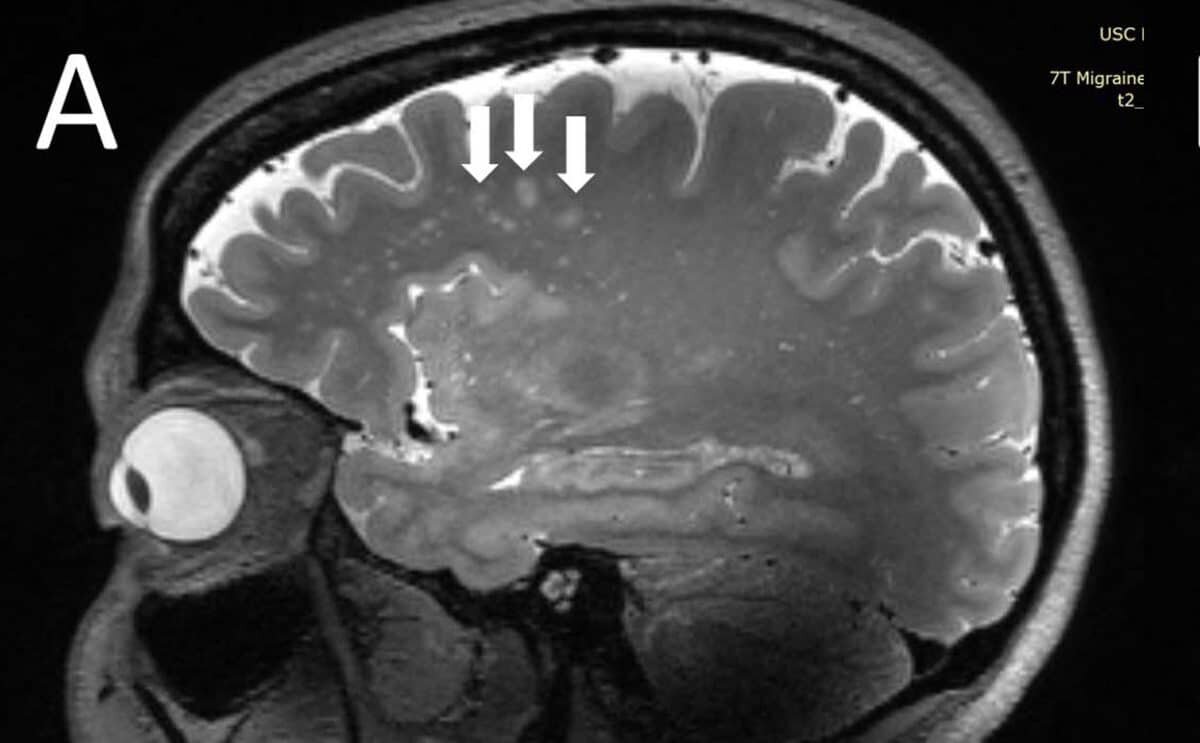

Изменения в мозге при мигрени / © RSNA and Wilson Xu